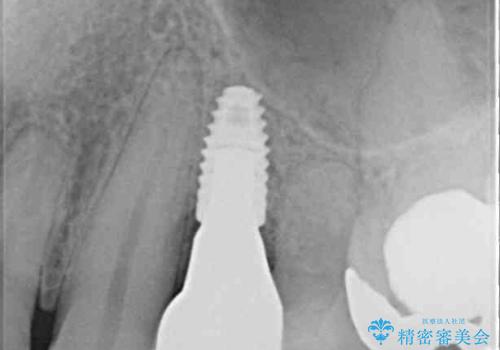

より審美的で、より機能的に優れた治療をご希望とのことであったので、ジルコニアカスタムアバットメントを用いたインプラント治療を行うこととしました。

ジルコニアカスタムアバットメントは、歯肉ラインに金属が見えにくいというだけでなく、クラウンを装着する土台の形が天然歯と近い形態となるため、清掃性が高く歯肉が腫れにくいというメリットがあります。

インプラントは、人工骨を用いた際の骨誘導能が比較的高いとさせるストローマン社のSLActiveを使用しました。